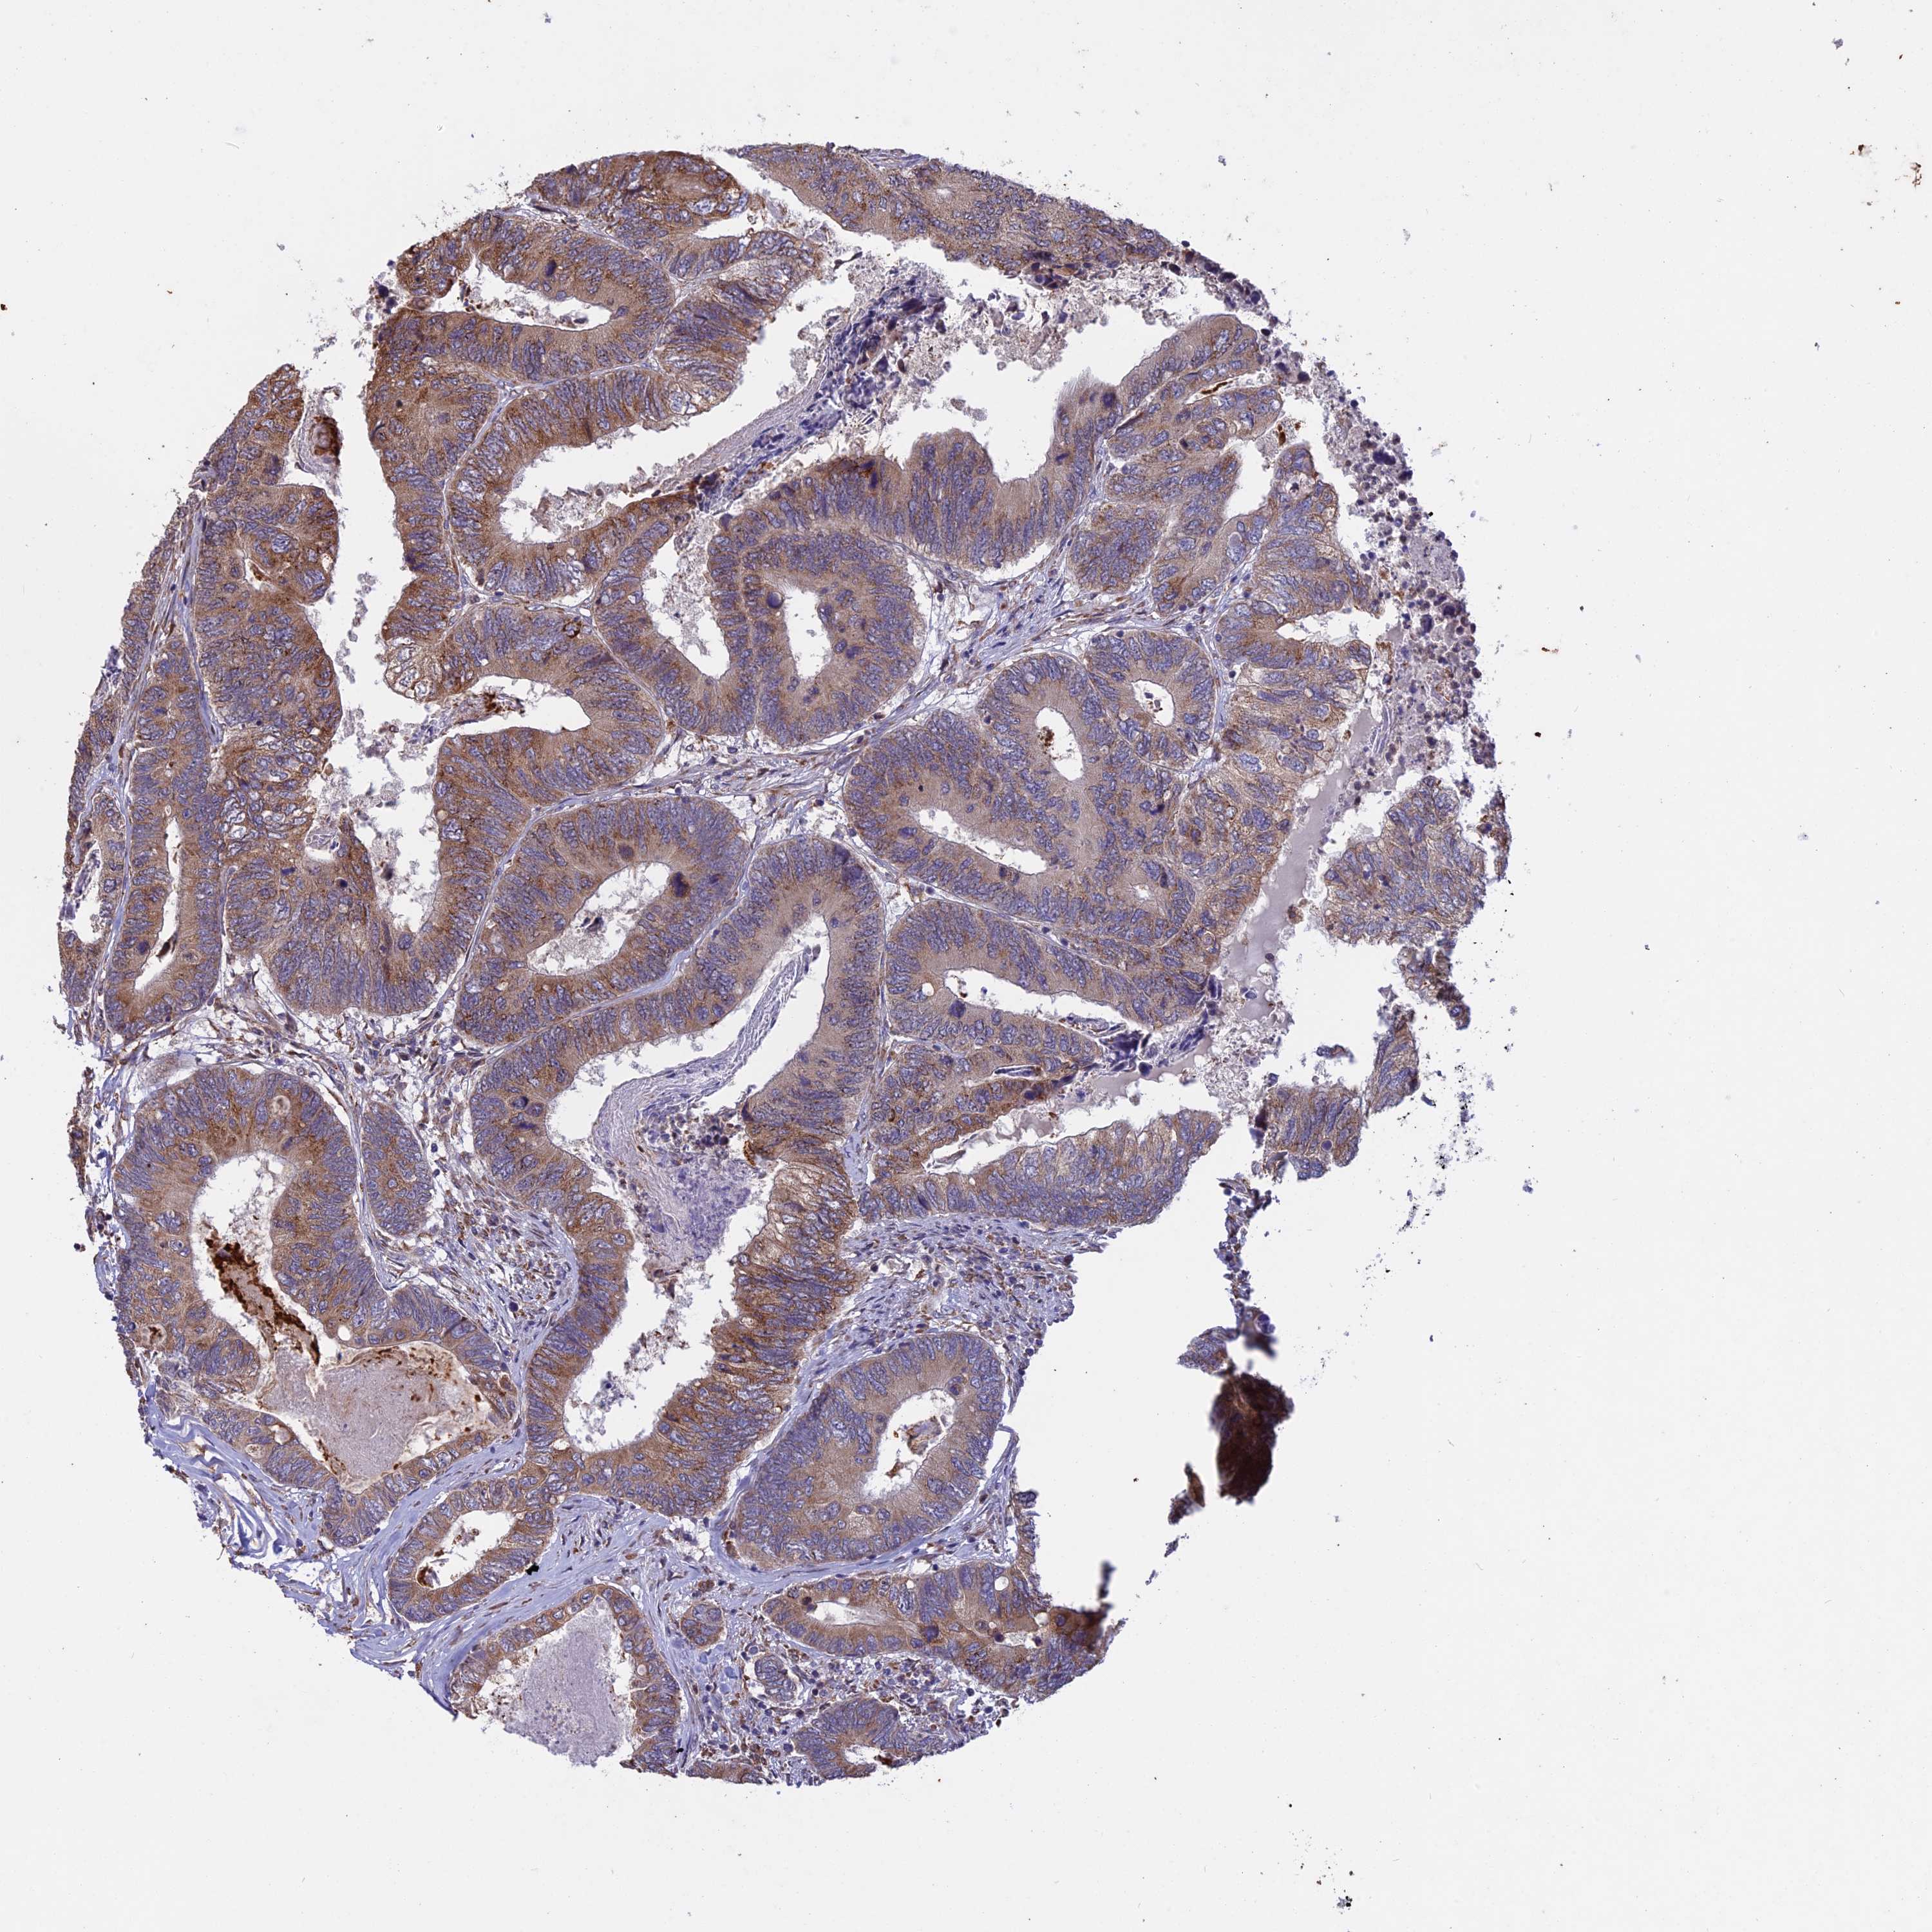

CANCER COLORECTAL CANCER Show tissue menu

Colorectal cancer

Human cancer

Colon adenocarcinoma